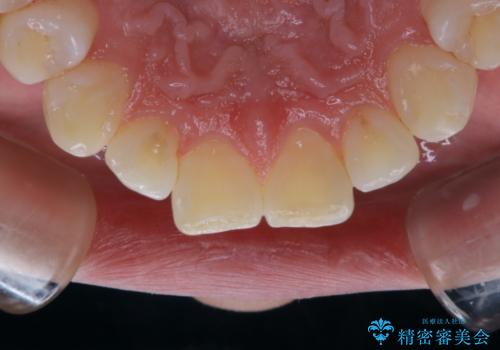

前歯の着色をPMTCできれいに